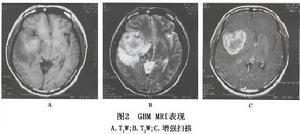

3.MRI檢查 腫瘤在T1加權圖像上呈低信號,T2W像為高信號的邊界不清的腫瘤影(圖2),與鄰近腦組織不容易區分,占位效應十分明顯。腫瘤內若有較大的壞死區則呈更低信號,若有出血呈高信號。胼胝體常受累 中線結構如縱裂池可變形、變窄或移位。腫瘤在T2加權像呈混雜信號,以高信號為主,散在性分布低與等信號。注射 Gd-DTPA 後腫瘤十分顯著的對比增強使得腫瘤與鄰近結構有明確的分界,且好發在腦深部,是較為特徵性的表現。